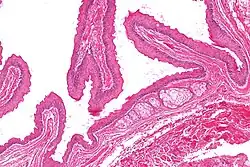

| Micrograph of a steatocystoma showing the characteristic corrugated eosinophilic lining. H&E stain | |

Steatocystoma simplex is a skin condition characterized by simple cysts forming in the ducts of sebaceous glands of the skin. It may be sporadic or hereditary.[1] It occurs with equal frequency in adult women and men, and cysts are typically found on the face, trunk, or extremities.[2]: 679 It is related to Steatocystoma multiplex.[3]